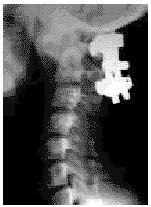

患者 男,15岁。于1997年初无明显诱因出现头颈部疼痛,活动受限。曾在外院拍摄X线片诊断为“寰枢椎半脱位”。经抗炎、头颈牵引复位及头颈胸石膏固定等治疗不见缓解。于1998年5月20日收入院治疗。查体:一般情况尚可,神志清。头颈部活动受限,伴有斜颈畸形。枢椎棘突压痛,四肢肌肉感觉、运动均正常。颈部X线片显示:寰枢椎半脱位(图1)。于1998年5月27日在气管插管全麻下行经颈后路寰枢椎固定融合术(Cotrel-Dubousset Instrumentation,C-D棒)。

图1 寰枢椎半脱位术前侧位X线片